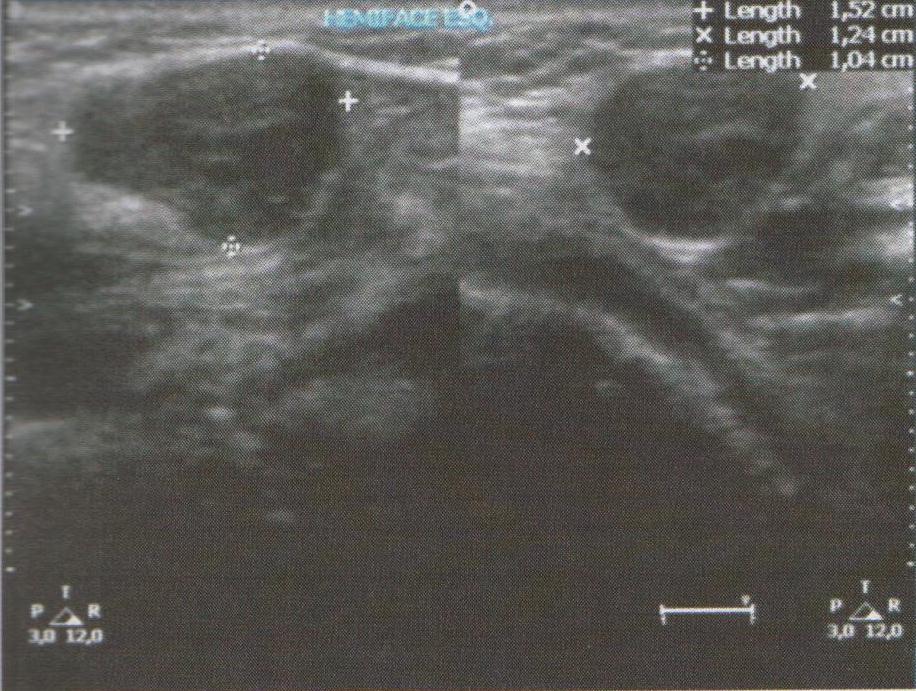

Myoepithelioma is a benign tumor of the salivary gland that mainly affects the parotid gland. The presence of an accessory parotid gland is an anatomical variation and neoplasms in this structure are extremely rare. This paper describes a case of a myoepithelioma arising in the accessory parotid gland of a 29-year-old woman. To the author´s knowledge this is the seventh case reported in English. The patient´s complaint was about a five year growing mass in the left cheek with a sudden growth outbreak. The patient underwent surgery via an intra-oral approach and the histopathology and the immunohistochemistry disclosed a myoepithelioma.